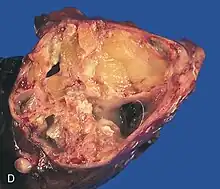

A mature teratoma is a grade 0 teratoma. They are highly variable in form and histology, and may be solid, cystic, or a combination of the two. A mature teratoma often contains several different types of tissue such as skin, muscle, and bone. Skin may surround a cyst and grow abundant hair (see dermoid cyst). Mature teratomas generally are benign, with 0.17-2% of mature cystic teratomas becoming malignant.[16]

Dermoid cyst

A dermoid cyst is a mature cystic teratoma containing hair (sometimes very abundant) and other structures characteristic of normal skin and other tissues derived from the ectoderm. The term is most often applied to teratoma on the skull sutures and in the ovaries of females.